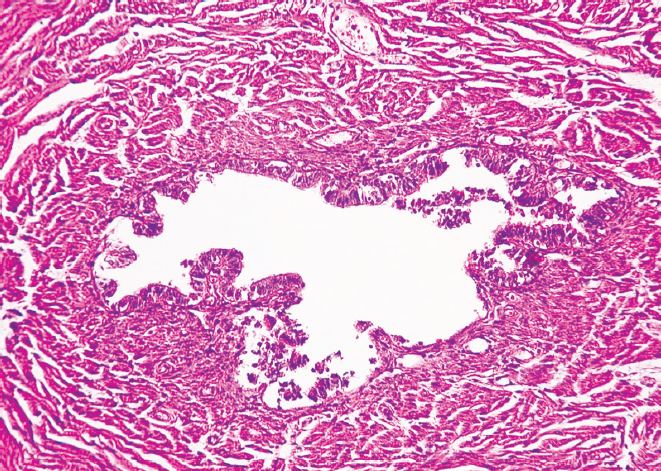

Гистологическое исследование препаратов показало, что в молодом возрасте слизистая оболочка перешейка и воронки маточных труб образует множественные продольные складки. Она представлена однослойным столбчатым эпителием и собственной пластинкой, которая образована рыхлой соединительной тканью. По ходу маточной трубы реснитчатые и секреторные эпителиоциты (экзокриноциты) располагаются неравномерно — реснитчатые преобладают в воронке маточной трубы, а секреторные — в области ее перешейка. Мышечная оболочка состоит из циркулярного и продольного слоев (рис. 1, 2).

Рис. 2. Фрагмент воронки маточной трубы женщины в возрасте 25 лет. Окраска гематоксилином и эозином, увел. ×10